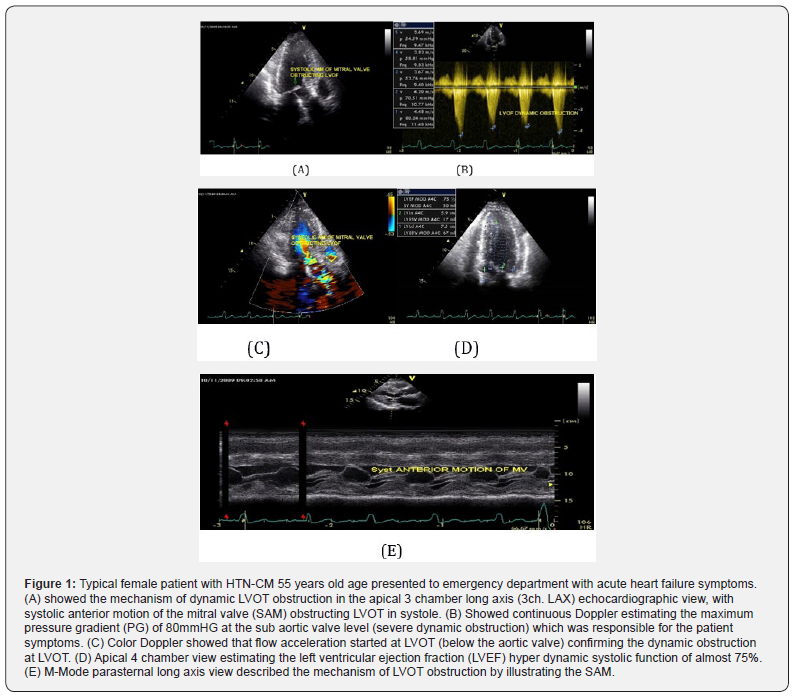

Both hypertrophic cardiomyopathy (HCM) and hypertensive heart disease (HHD) present left ventricular hypertrophy (LVH), but the prognosis varies. Nevertheless, the feasibility of distinguishing these two conditions is limited by the fact that overlapping LVH and diverse forms of HCM can often lead to diagnostic challenge when diagnosis is based on a single morphological index. Diagnosis is more difficult in a patient with a history of hypertension and with left ventricular wall thickness between 11 and 15 mm, (see Figures 1 & 2).

After 4 weeks of Full dose of Beta blockers therapy Metoprolol 200mg daily, the patient become a symptomatic and PG at LVOT returned back to normal values, see (Figure 2).

See (Figures 1 and 2) A thorough history and physical should be performed. All patients should be asked about family history of HOCM and of sudden cardiac death. A majority of hypertensive and HCM patients are asymptomatic. Dyspnea is the most common complaint among symptomatic patients. Patients may also complain of pre syncope, syncope, angina, palpitations (secondary to arrhythmia), or dizziness. Symptoms will frequently be exacerbated by exertion. Severe cases will present like congestive heart failure with paroxysmal nocturnal dyspnea, leg edema, and orthopnea. The most devastating presentation is sudden cardiac death [15].

Persistent systemic hypertension induces LVH, fibrosis, diastolic dysfunction, and an increase in the activation of the renin angiotensin aldosterone system (RAAS), which leads to congestive heart failure [16]. One of the mechanisms of heart failure in patients with hypertension is LV diastolic dysfunction. LV diastolic dysfunction associated with hypertension is morphologically characterized by LV wall thickening and increased Left Atrial (LA) volume. In advanced stages, hypertension induces eccentric LVH and LV systolic dysfunction, see Figure (1) [17].